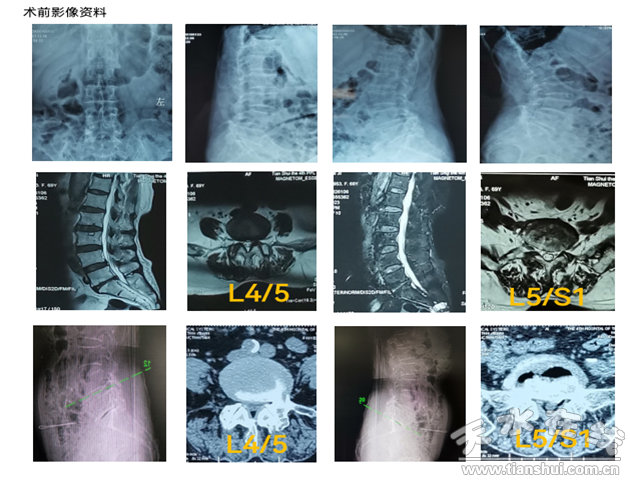

患者70歲,女性,主訴腰痛伴左下肢疼痛麻木1年,加重2月余;颊咝凶200米后出現(xiàn)腰痛及左下肢疼痛麻木,必須下蹲休息數(shù)分鐘后才能繼續(xù)行走,近2月來進行性加重,近一周疼痛加重?zé)o法下地行走。X線、CT及MRI 顯示:腰4/5、L5/S1節(jié)段椎管狹窄,神經(jīng)根和硬膜囊受壓,在我市多家醫(yī)院保守治療無效,嚴(yán)重影響患者生活質(zhì)量。

患者住院后科室副主任韋瑋通過詢問病史,仔細體格檢查,結(jié)合影像學(xué)檢查,和患者及家屬充分交流溝通,經(jīng)甘肅省中醫(yī)院脊柱微創(chuàng)骨科王想福主任醫(yī)師會診后,確定該患者適合在全麻下行UBE手術(shù)。因患者影像學(xué)表現(xiàn)雙節(jié)段狹窄,但患者臨床表現(xiàn)是L5神經(jīng)根受壓體征,術(shù)前先進行左側(cè)L5神經(jīng)根阻滯,患者左下肢疼痛即刻緩解約80%,明確責(zé)任間隙后,隨后在UBE下行L4/5椎管減壓術(shù),歷經(jīng)1小時手術(shù)順利完成,麻醉清醒后患者左下肢疼痛消失,活動良好。術(shù)后第二日即佩戴腰圍下地活動,無疼痛不適。